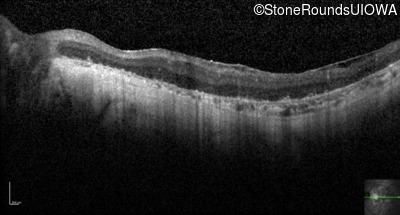

Optical Coherence Tomography - Left - Hand Motion 1' sc

Exemplar / OCT Stack

OCT Stack